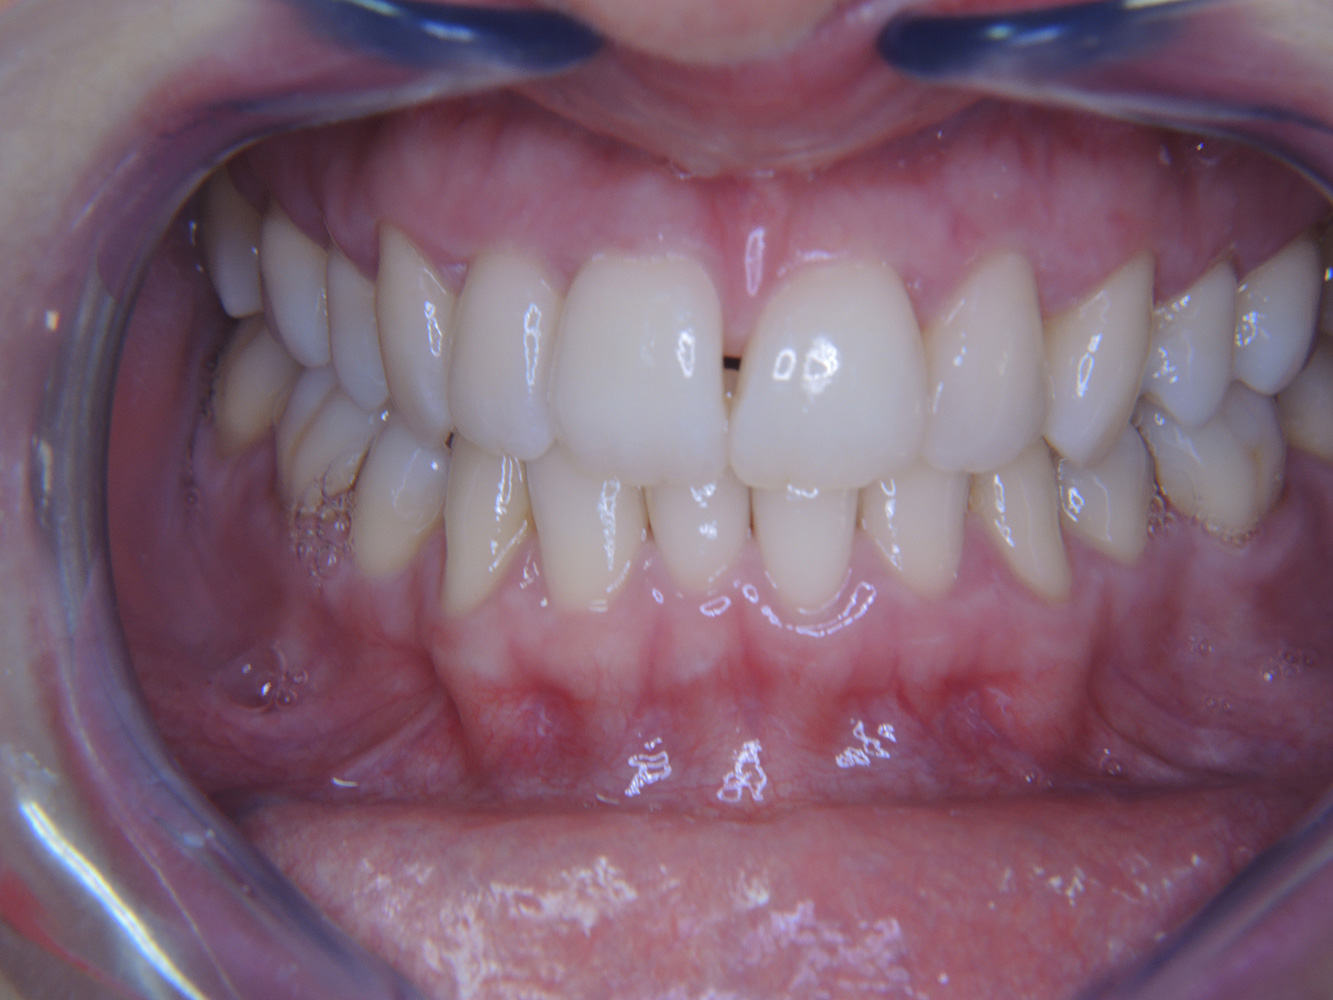

A 51-year old diabetic patient presents with good oral health at a prevention session. Her blood sugar levels are stable at HbA1c = 6.2%, and thus her condition is thought to be sufficiently managed with the antidiabetic drug metformin. The patient has no existing restorations or early oral disease. Using the dental results, it is possible to determine gingivitis in spite of an otherwise stable condition.